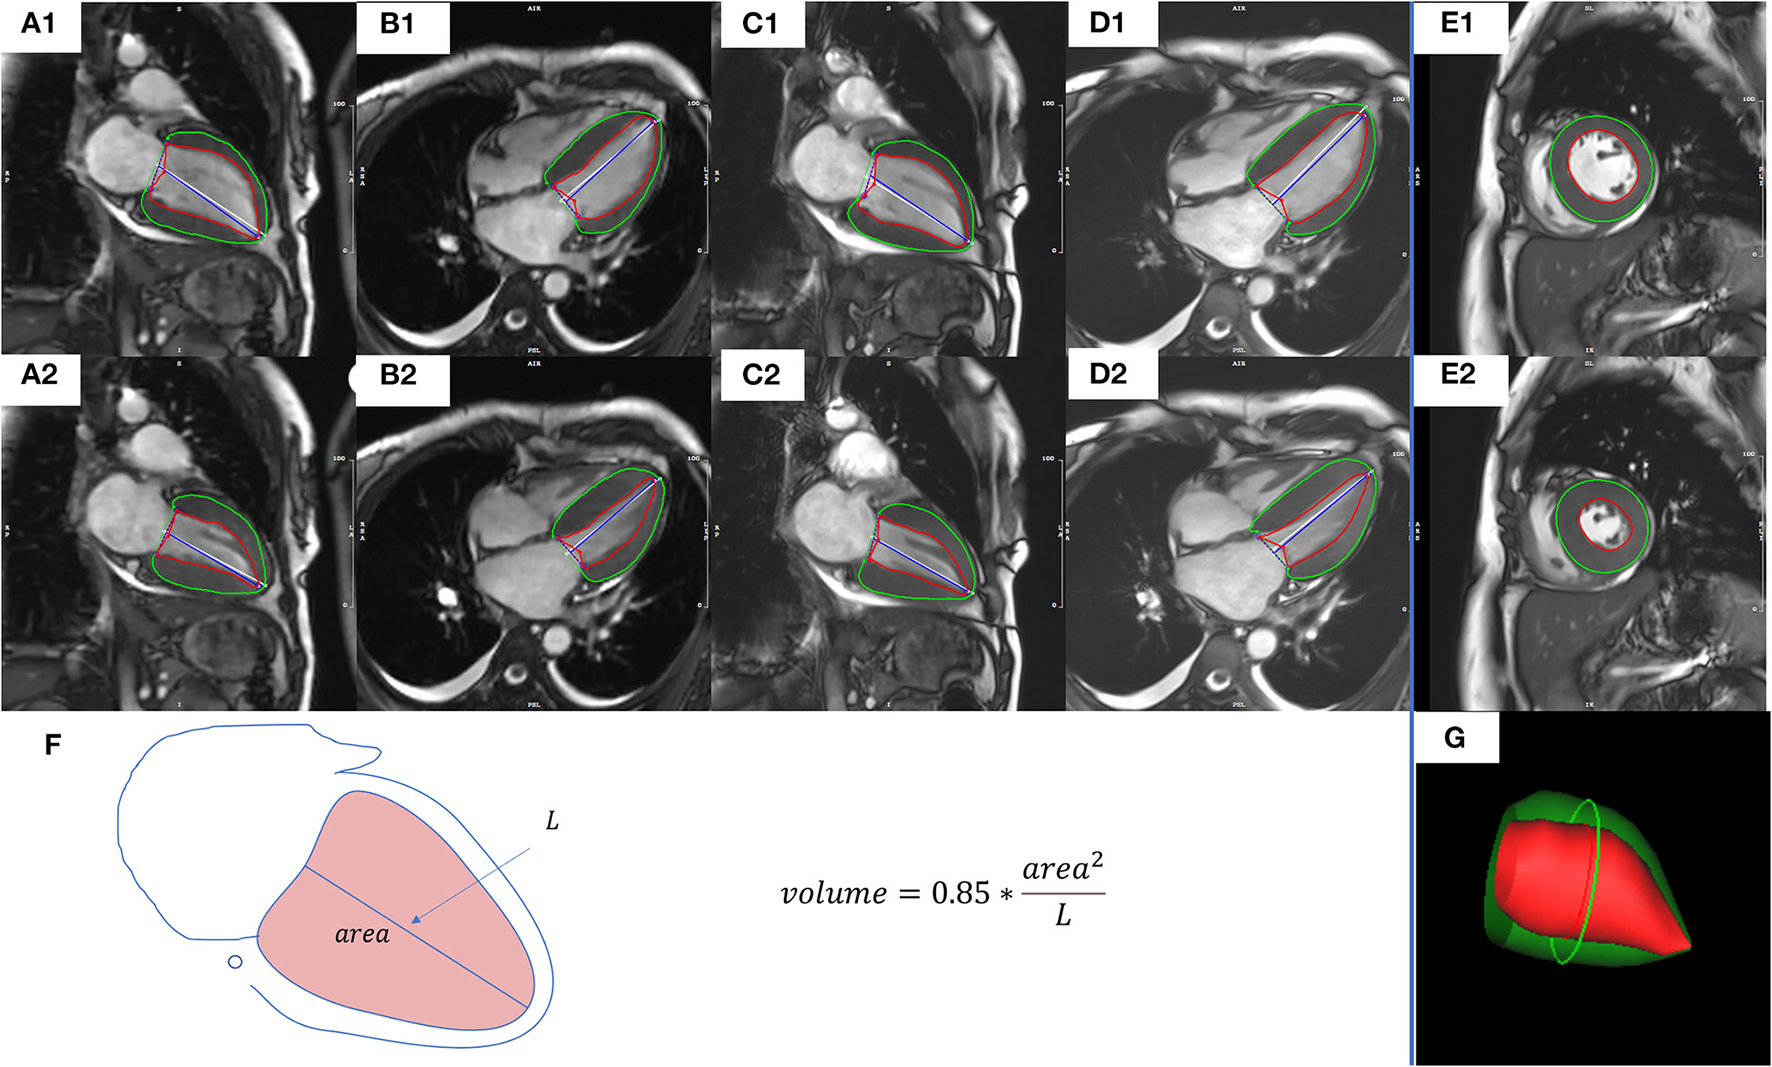

Assessment of end-diastolic volume (EDV), end-systolic volume (ESV), stroke volume (SV), ejection fraction (EF), cardiac output (CO), cardiac index (CI), and LV mass (LVM) were performed using dedicated CMR postprocessing software (CVI42; Circle Cardiovascular Imaging, Inc., Calgary, Canada). For all patients with NSR, the 5 methods used for functional assessment were as follows: CSRT cine images combined with AL method in 2CH (CSRT2CH_AL) or 4CH (CSRT4CH_AL), segmented cine images combined with AL method in 2CH (Seg2CH_AL) or 4CH (Seg4CH_AL), and segmented cine images combined with Simpson's rule in SA (SegSA_Simpson) (Figure 2). The AL method is based on a rotational ellipsoid with the volume calculated using the formula: . The ‘area' in the formula was obtained from the 2CH or 4CH view; the ‘L' was measured as the length of the line from the LV apex to the center of the mitral valve annulus in the same view (16, 18). In Simpson's rule, the LV volume is estimated as the sum of the cross-sectional area of multiple single slices multiplied by the slice thickness plus gap. The endo- and epicardial contours were detected automatically with manual correction. The endocardial trabeculations and papillary muscles were included in the ventricular volume. End-diastolic and end-systolic phases were defined manually, based on the smallest and largest LV cavities during the cardiac cycle (19). For all patients with AF, LV functional parameters and heart rate (HR) for every consecutive heartbeat up to 4 or 5 heartbeats were measured using CSRT2CH_AL. Then, the mean, maximum, and minimum values of each parameter from the 4~5 consecutive heartbeats were calculated as three new quantitative indices for each functional parameter. To test intra-observer variability, the functional analysis was repeated two months later by the same radiologist, for a subset of 20 randomly selected participants with NSR and all participants with AF. The inter-observer variability also was tested by another radiologist (one with 5 years of experience) in the same subset of participants.

Figure 2

Representative images and measures of LV function from a representative study patient. CSRT2CH_AL (A1,A2) or CSRT4CH_AL (B1,B2) utilized CSRT cine combined with the 2CH or 4CH AL method. Seg2CH_AL (C1,C2) or Seg4CH_AL (D1,D2) utilized segmented cine combined with the 2CH or 4CH AL method. SegSA_Simpson (E1,E2) utilized segmented cine combined with SA Simpson method. The AL method is based on a rotational ellipsoid with a volume calculated using the formula: (F). The ‘area' in the formula was obtained from the 2CH or 4CH view; the ‘L' was measured as the length of the line from the LV apex to the mitral valve annulus in the same view. In Simpson's rule, the LV volume is estimated as the sum of the cross-sectional area of multiple single slices multiplied by the slice thickness plus gap. The visualization of end-diastolic volume measured by Simpson's rule was shown in (G). End-diastolic (upper row) and end-systolic (middle row) phases were defined manually, based on the smallest and largest LV cavities during the cardiac cycle. The endocardial contours (red) and epicardial contours (green) were drawn automatically with manual correction. CSRT2CH_AL, area-length method using two-chamber compressed sensing real time cine; CSRT4CH_AL, area-length method using four-chamber compressed sensing real time cine; Seg2CH_AL, area-length method using two-chamber segmented cine; CSRT4CH_AL, area-length method using four-chamber segmented cine; AL, area-length; SegSA_Simpson, Simpson method using short axis segmented cine, 2CH, two-chamber; 4CH, four-chamber; SA, short axis. LV, left ventricular.